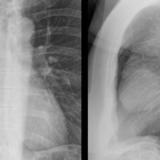

Case 8b Thymoma Lat

Date: 03/27/2009

Views: 14097